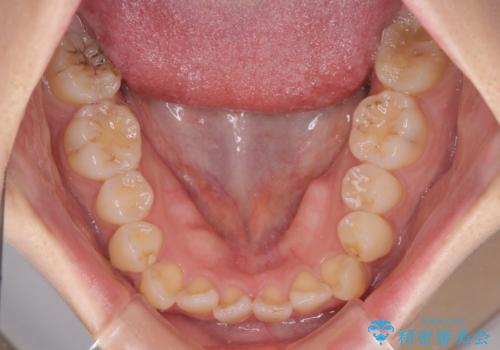

- 八重歯や前歯の捻転とクロスバイトが気になり、インビザラインによる矯正治療を希望して来院された患者様です。

上顎側切歯(上の真ん中から2番目の歯)が舌側転位している場合、無理して動かそうとすると歯髄壊死を起こすリスクが高い印象があります。

インビザライン単体でも治療は可能ですが、安全策としてインビザラインで歯列を移動する前に上顎前歯をワイヤー矯正で整え、その後上下歯列をインビザラインにて矯正治療を行うこととしました。

舌側転位している側切歯特有の、切縁の位置が不揃いであったり、根元が内側に引っ込んだ状態であったりという、インビザライン独特の仕上がりになることなく、きれいに整った歯列とすることができました。